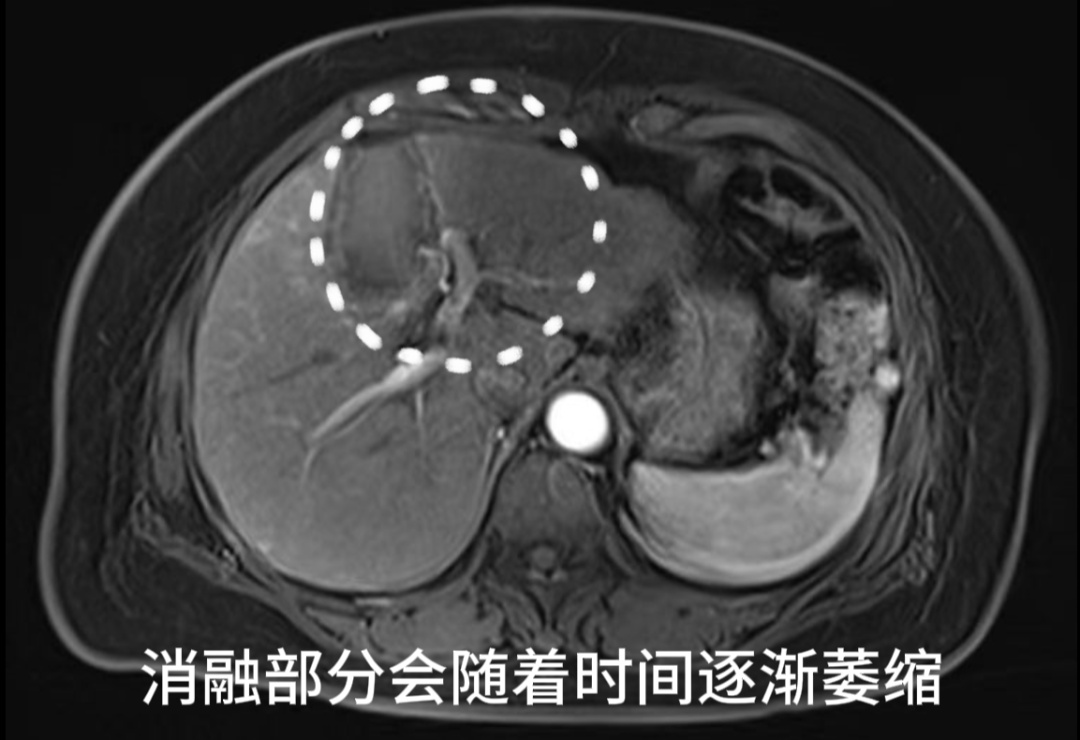

患者术后第二天MR

复查结果提示未见肝内有强化病灶,肿瘤完全失去了活性。经外周静脉注射造影剂Sonazoid后,病灶区域始终未灌注区,显示消融效果满意。